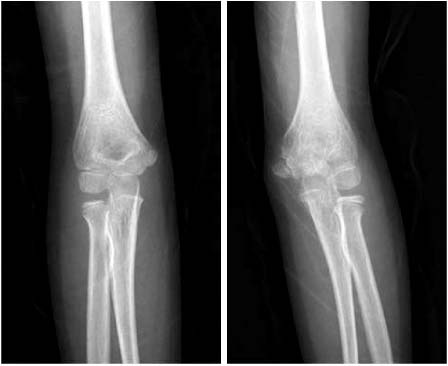

Fx: Fracture, Dx: Diagnosis, MCF: Medial condyle fracture, MRI: Magnetic resonance imaging, Intraop.: Intraoperative, OR/IF: Open reduction and internal fixation, LOM: Limitation of motion, ROM: Range of motion.